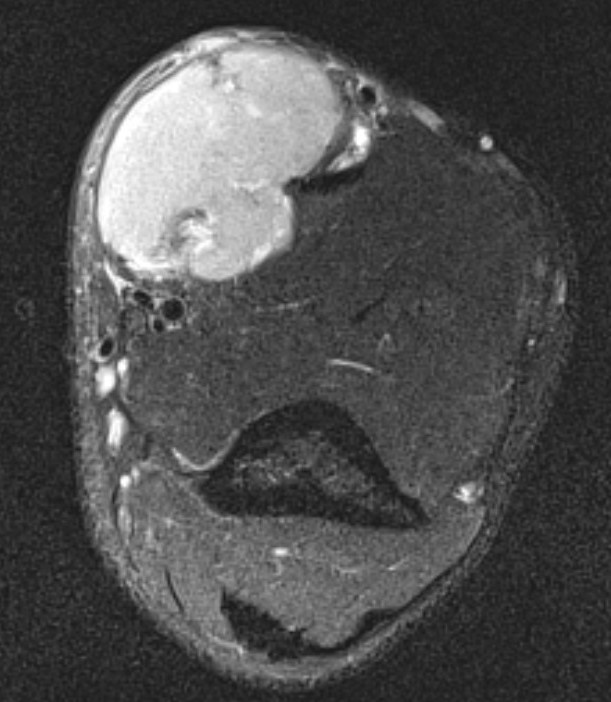

MRI

Heterogenous mass, low signal intensity T1, high signal intensity T2

- may have characteristic triple signal intensity

- area hyperintensity, isointensity and hypointensity

Knee

Heterogenous mass, not communicating with joint

DDx Baker's cyst